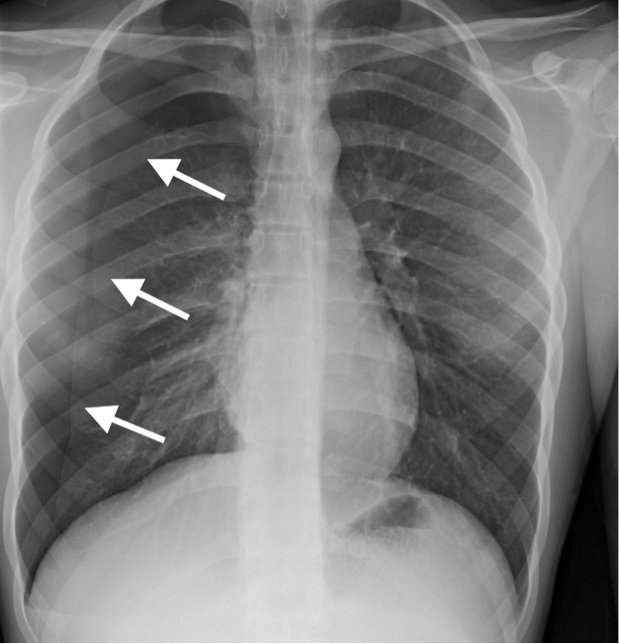

A 16-year-old male with asthma was brought to the emergency department by his parents for increasing right-sided chest pain associated with cough and mild dyspnea over the past week. Albuterol inhaler did not provide relief. He denied recent trauma, fever, sweats, and chills. The patient’s vitals and oxygen saturations were stable. Physical exam revealed a tall, slender body habitus with no signs of chest wall injuries. Bilateral breath sounds were present, but slightly diminished on the right. A chest radiograph was ordered to determine the etiology of the patient’s symptoms.

Significant findings:

Initial chest radiograph showed a 50% right-sided pneumothorax with no mediastinal shift, which can be identified by the sharp line representing the pleural lung edge (see arrows) and lack of peripheral lung markings extending to the chest wall. While difficult to accurately estimate volume from a two-dimensional image, a 2 cm pneumothorax seen on chest radiograph correlates to approximately 50% volume.1 The patient underwent insertion of a pigtail pleural drain on the right and repeat chest radiograph showed resolution of previously seen pneumothorax. Ultimately the pigtail drain was removed and chest radiograph showed clear lung fields without evidence of residual pneumothorax or pleural effusion.